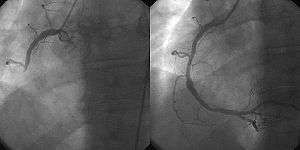

![]() A coronary angiogram (an X-ray with radio-opaque contrast in the coronary arteries) that shows the left coronary circulation. The distal left main coronary artery (LMCA) is in the left upper quadrant of the image. Its main branches (also visible) are the left circumflex artery (LCX), which courses top-to-bottom initially and then toward the centre/bottom, and the left anterior descending (LAD) artery, which courses from left-to-right on the image and then courses down the middle of the image to project underneath of the distal LCX. The LAD, as is usual, has two large diagonal branches, which arise at the centre-top of the image and course toward the centre/right of the image. | |